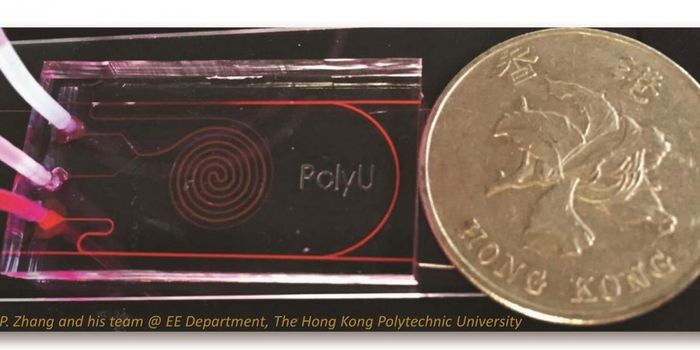

FEB 25, 2019TechnologyA new study published in the journal Microsystems & Nanoengineering shows the development of a device that can detec ...